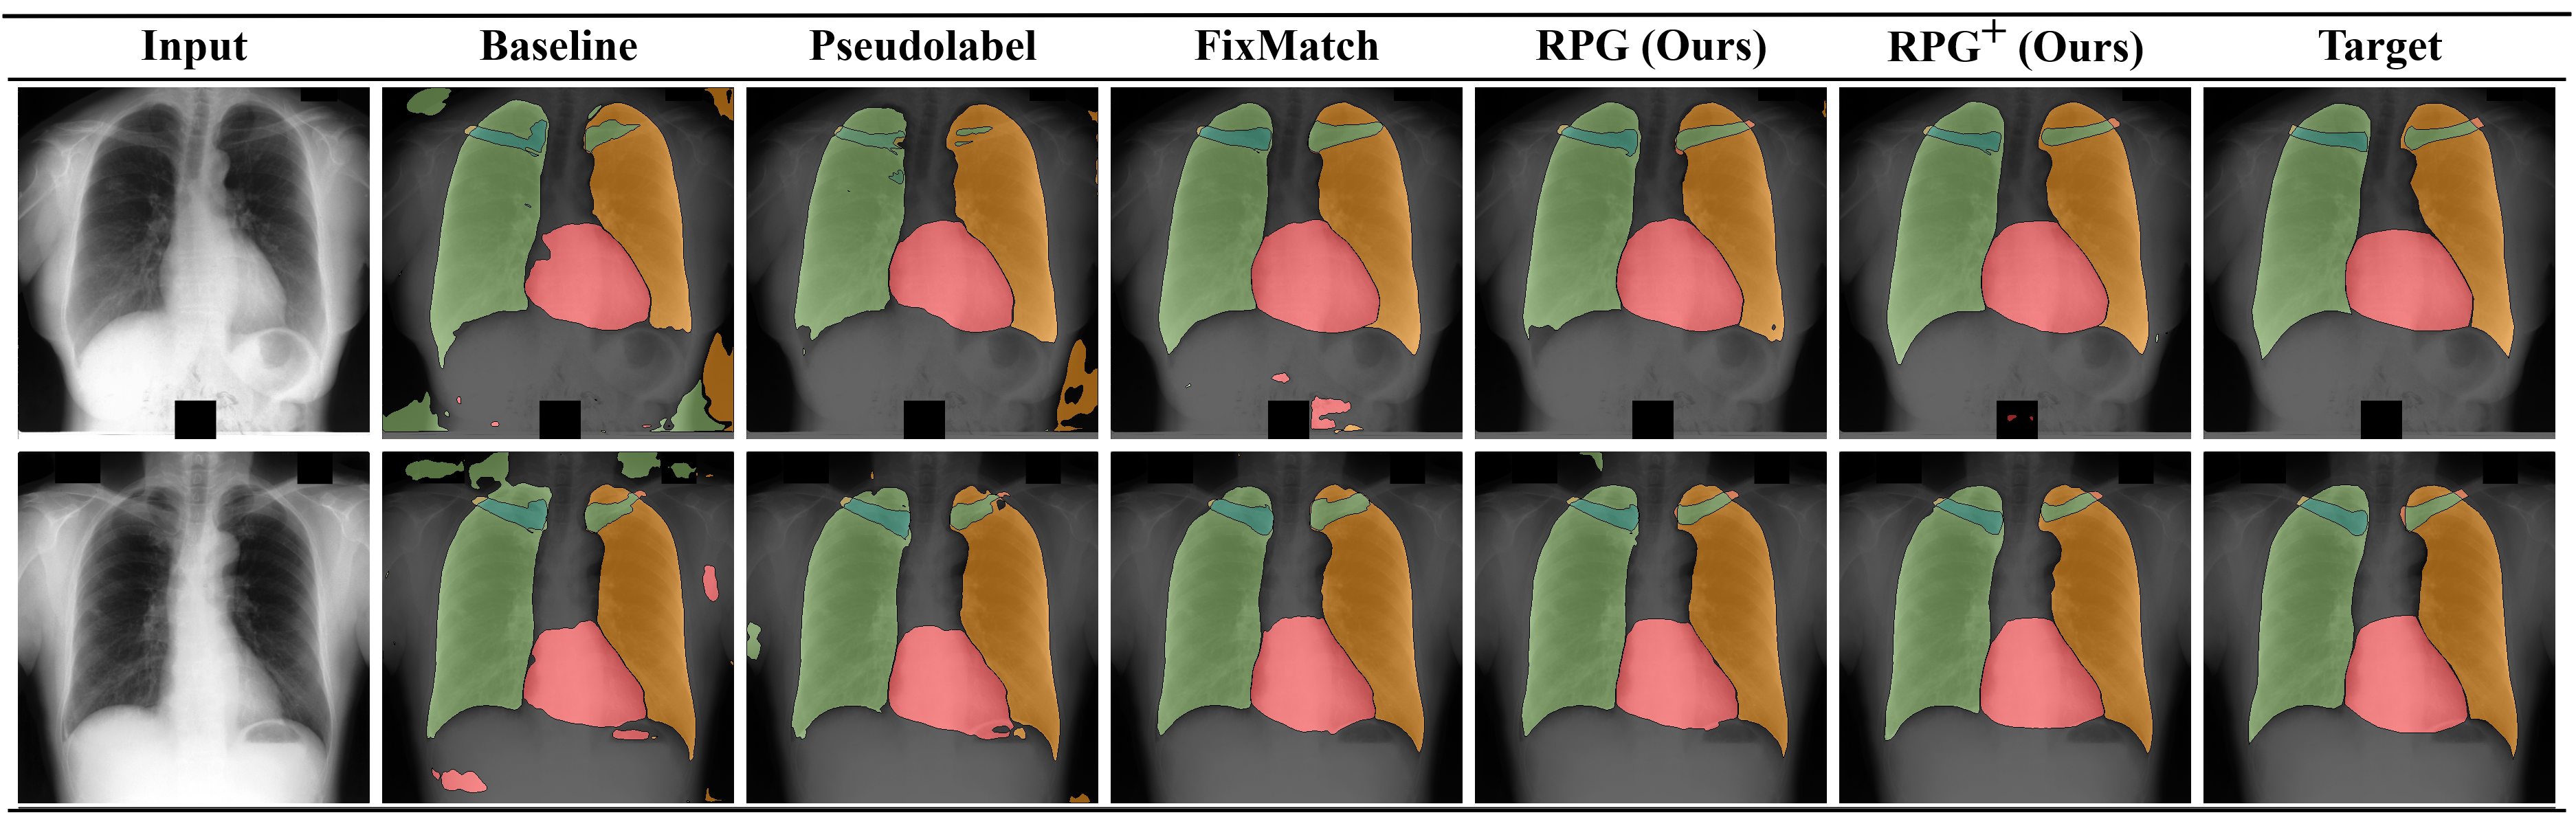

Refer to caption

Figure 3: Qualitative Segmentation Results on the JSRT (Shiraishi et al. 2000) dataset for Nl=6subscript𝑁𝑙6N_{l}=6.

We further demonstrate the class-wise performance for three annotated samples on the top of Table 4. We see that the baseline as well as pseudo labeling struggle with less common classes like the clavicles. FixMatch shows considerable improvements for the classes with more annotated pixels, while the performance for the clavicles only slightly improves. RPG𝑅𝑃𝐺RPG also improves over the baseline for heart and lungs, but shows significant improvements for the difficult clavicles. Furthermore, RPG+𝑅𝑃superscript𝐺RPG^{+} combines the aspects of RPG𝑅𝑃𝐺RPG and augmentation-based consistency regularization, which noticeably improves all categories apart from the right clavicle with gains up to absolute 26%percent2626\% over the baseline. We display segmentation predictions in Fig. 3, where class-wise shortcomings of the different methods become visible.